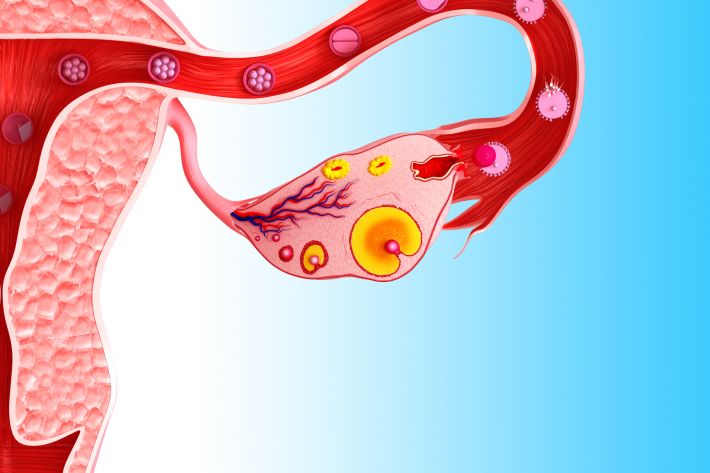

بین روزهای ششم و چهاردهم چرخه قاعدگی، FSH باعث میشود فولیکولها (کیسههای کوچک در تخمدانها که حاوی یک تخمک در حال رشد هستند) در تخمدان شروع به بلوغ کنند. در طی روزهای 10 تا 14 چرخه، تنها یکی از فولیکولهای در حال رشد تخمک کاملا بالغ را تشکیل میدهد. در حدود روز چهاردهم چرخه قاعدگی، افزایش ناگهانی LH باعث میشود که تخمدان، تخمک خود را آزاد کند. به این حالت تخمک گذاری میگویند.

پس از تخمک گذاری، تخمک سفر پنج روزه خود را از طریق لوله فالوپ به سمت رحم آغاز میکند. همانطور که تخمک از طریق لوله فالوپ حرکت میکند، سطح پروژسترون، هورمون دیگری، در بدن افزایش مییابد که به آماده سازی پوشش رحم برای بارداری کمک کند.